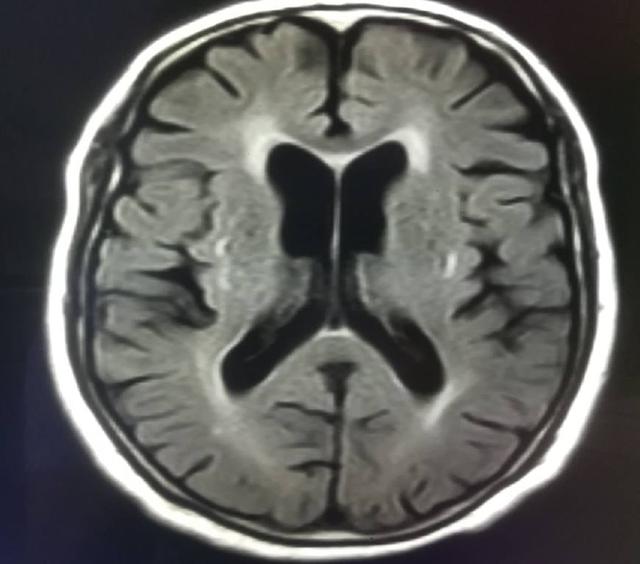

隨著年齡的增長,人體自然地會丟失一些腦細胞,但是這個過程相當緩慢。當創(chuàng)傷、疾病或感染引起腦萎縮時,腦細胞丟失的速度更快,受到破壞更明顯。這種腦細胞(神經元)的異常丟失就叫做腦萎縮。那么腦萎縮是又什么引起的呢?

腦萎縮大多數考慮是由于神經細胞變性所引起,患者一般表現為腦體積縮小,包括大腦萎縮和小腦萎縮。患者可能是由于長期失眠或者是壓力大引起,也可能是長期大量飲酒引起。

如果患者有長期慢性腦供血不足時,也可能會出現。也可能是一種老年性的腦改變。對于成年人來說,如果出現了腦萎縮,很有可能是由于頭部的器質性疾病所引起的,如顱內感染或者是腦外傷,還有硬膜外血腫都會導致腦實質受壓,從而引發(fā)腦萎縮,腦萎縮與年齡也有一定的關聯,正常大腦和機器是一樣的,也會出現老化的情況,就會出現萎縮。

綜上所述,腦萎縮的原因非常多,例如遺傳、腦外傷、腦卒中、腦炎、腦膜炎、腦血管畸形、腦部腫瘤、癲癇長期發(fā)作、飲酒過度、營養(yǎng)不良、甲狀腺功能性疾病、煤氣中毒、酒精中毒、腦動脈硬化、腦缺氧、腦缺血均可引起腦實質破壞或神經細胞的萎縮、變形、消失,臨床上高血壓、糖耐量異常、血脂異常、腦小動脈硬化,都是老年性腦萎縮的重要危險因素。